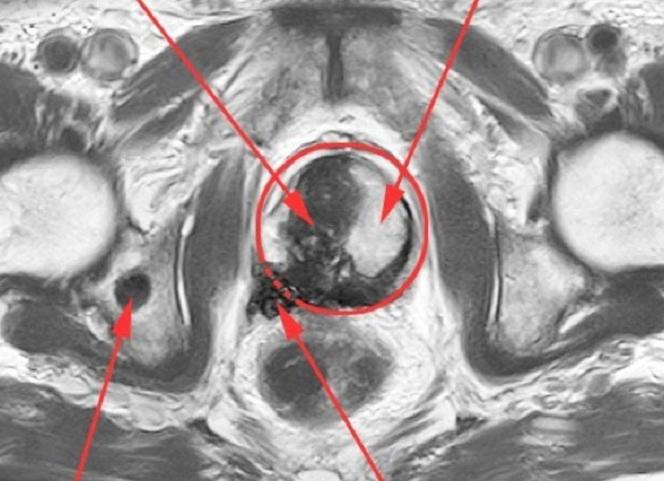

Квантовая физика, математика, биология, криогеника, химия и электроника сплелись единым узором, чтобы воплотиться в железе и показать настоящий внутренний мир человека, и даже, ни много ни мало, прочитать его мысли. Электроника таких аппаратов, по надежности и сложности может сравниться разве что с космической. Эта статья посвящается оборудованию и принципам работы магнитно-резонансных томографов. В области современного томографостроения лидируют мастодонты электронного мира: Siemens, General Electric, Philips, Hitachi. Только такие крупные компании могут позволить себе разработку столь сложного оборудования, стоимость которого как правило составляет десятки (почти сотни) миллионов рублей. Разумеется, ремонт такой дорогущей техники у официального представителя влетает в огромную копеечку владельцу аппарата (а они к слову в основном частные, а не государственные). Но не стоит отчаиваться! Также как и сервис-центры по ремонту ноутбуков, телефонов, чпу-станков, да собственно любой электроники существуют фирмы, занимающиеся ремонтом медицинского оборудования. В одной из таких фирм я и работаю, поэтому продемонстрирую вам интересную электронику и постараюсь описать ее функционал понятными словами. Подробнее ...